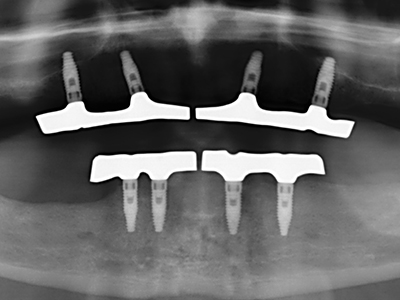

Fig. 11: la panoramica postoperatoria mostra l'accrescimento verticale e il rialzo del pavimento sinusale.

Fig. 12: dopo sei mesi di processo di guarigione, la cresta alveolare è vitale e sufficientemente dimensionata in tutti i piani.

Fig. 13: l'irrigazione adeguata con l'osso residuo largo 4 mm è essenziale durante l'incisione ossea di questo paziente di 52 anni.

Fig. 14: posizionamento di quattro impianti RSX conici (BEGO Implant Systems, Brema).

Fig. 15: la radiografia dopo un follow up di un anno mostra condizioni stabili a livello osseo.

Fig. 16: anche le condizioni intra-orali sono stabili, con l'incorporazione degli impianti nella gengiva cheratinizzata.